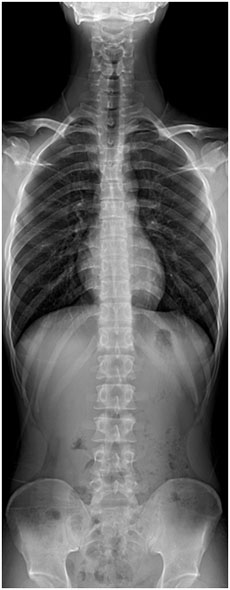

ÇÑÆíÀ¸·Î´Â °ñ°Ý°èÀÇ º¯È Áß ÁÖ¿äÇÑ ºÎºÐÀÎ °ñ´Ù°øÁõÀÇ Áõ°¡ ¶ÇÇÑ °°Àº ¾ç»óÀ» º¸À̰í ÀÖ¾î ³ë³â±â

°Ç°°ü¸®ÀÇ Áß¿äÇÑ ºÎºÐÀÌ µÇ°í ÀÖ½À´Ï´Ù.